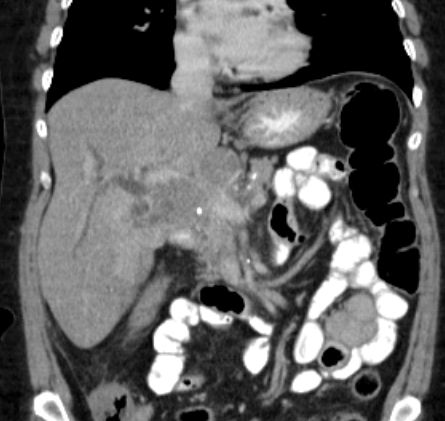

Leberhilus

69-jährige Frau, die mit Verschlussikterus eingeliefert wird. Im Leberhilus eine große Raumforderung. Erweierung der intrahepatischen Gallengänge. Seit einem Jahr chronischer Husten. Eine Untersuchung beim Lungenfacharzt ohne Befund. Nach ERCP und Stenteinlage Rückgang des Ikterus. Bronchoskopisch Nachweis eines kleinzelligen Tumors im rechten Unterlappenbronchus.